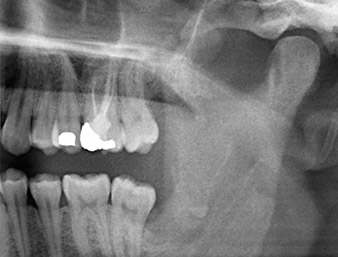

Tras una anestesia local y por conducción, el campo quirúrgico se abrió mediante los tejidos blandos para tener un acceso bucal-retromolar y se dejó expuesto (figura 3).